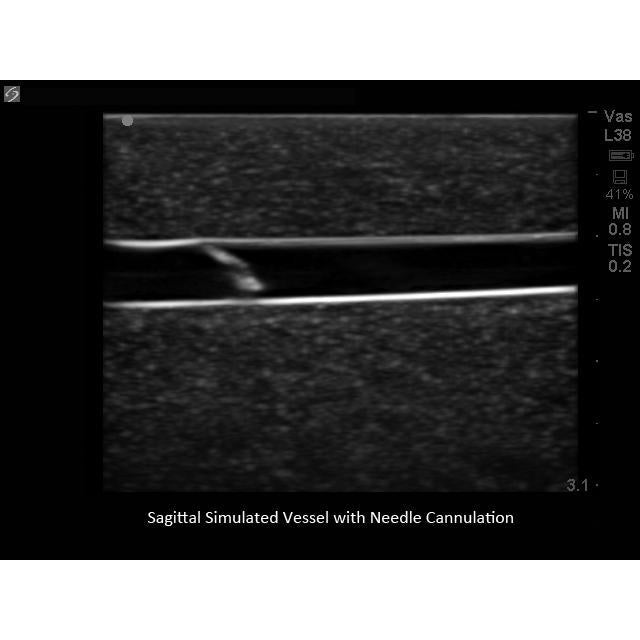

Our Branched 4 Vessel ultrasound guided vascular access training model contains a blood vessel that branches into 4 vessels positioned at differing depths and course throughout the model. Users can image the bifurcating vessels, track the course of the vessels, and guide needles into the targeted vessel using ultrasound imaging. Clinicians can gain experience acquiring and interpreting ultrasound images of blood vessels as well as developing the psychomotor skill associated with guiding needles to simulated vessels.

Our Branched 4 Vessel ultrasound guided vascular access training model contains a blood vessel that branches into 4 vessels positioned at differing depths and course throughout the model. Users can image the bifurcating vessels, track the course of the vessels, and guide needles into the targeted vessel using ultrasound imaging. Clinicians can gain experience acquiring and interpreting ultrasound images of blood vessels as well as developing the psychomotor skill associated with guiding needles to simulated vessels.

Practice imaging

skills such as; using ultrasound system controls, transducer positioning and movement, recognition of vessels in

soft tissue, using ultrasound to target individual linear vessels and using the more complex branched vessel anatomy

to refine and advance users approach for ultrasound guided vascular access procedures.

Excellent ultrasound imaging characteristics.

Gain experience by choosing to guide needles to individual vessels or for more advanced training, target overlapping branched vessels at different depths as you would experience in the human patient. Once users accurately access the vessels within the model, fluid flow provides the user with positive feedback that they have accessed the targeted vessel.